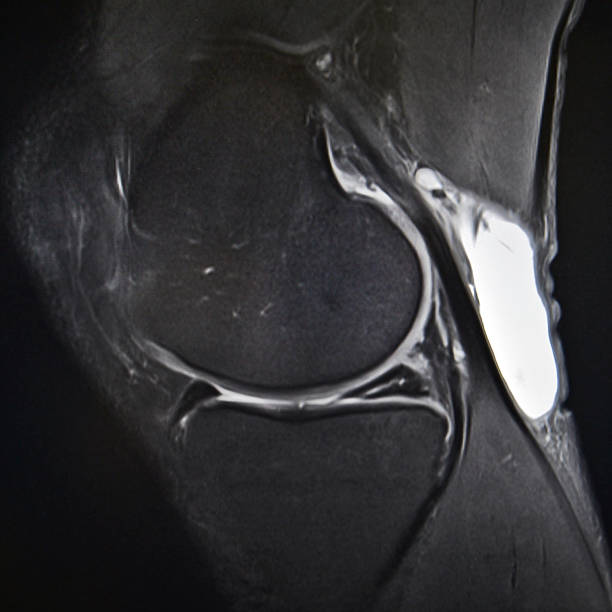

Ask any professional athlete and they will tell you a torn meniscus is one of the most common knee injuries. That’s because any activity – sports-related or otherwise – that causes you to forcefully twist or rotate your knee, can result in a torn meniscus.

The meniscus is the C-shaped piece of tough, rubbery cartilage between the shinbone and thighbone that acts as a shock-absorbing cushion. When you sustain a torn meniscus, it causes pain, swelling, and stiffness within 24 hours, and you might also feel other signs and symptoms that include:

If left untreated, a part of a torn meniscus can come loose and slip into the joint. If this happens, you may need surgery to restore full knee function. The meniscus tear can also increase in size and lead to unnecessary complications, such as arthritis. This is why you should promptly consult with an orthopedist if you suspect you have sustained a meniscus tear.